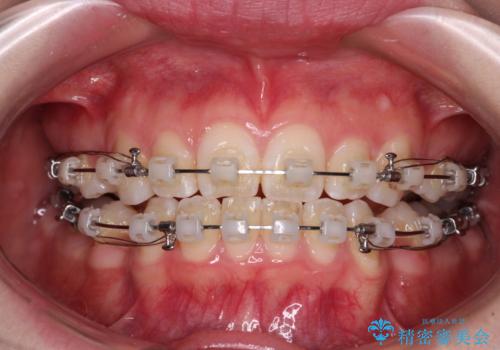

- 矯正装置

- クリアブラケット

- 治療期間

- 2年4ヶ月

- 治療回数

- 10-30回